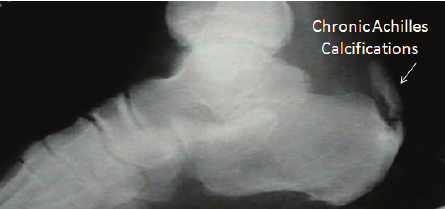

여기다가

혈액순환까지 잘 되지 않으면

석회가 침착되기 시작합니다.

이를

[아킬레스건의 석회화, 석회성 건염]

이라고 합니다.

특히 아킬레스건은

어깨의 극상건과 함께

혈액순환이 안되기로

악명 높은 곳입니다.